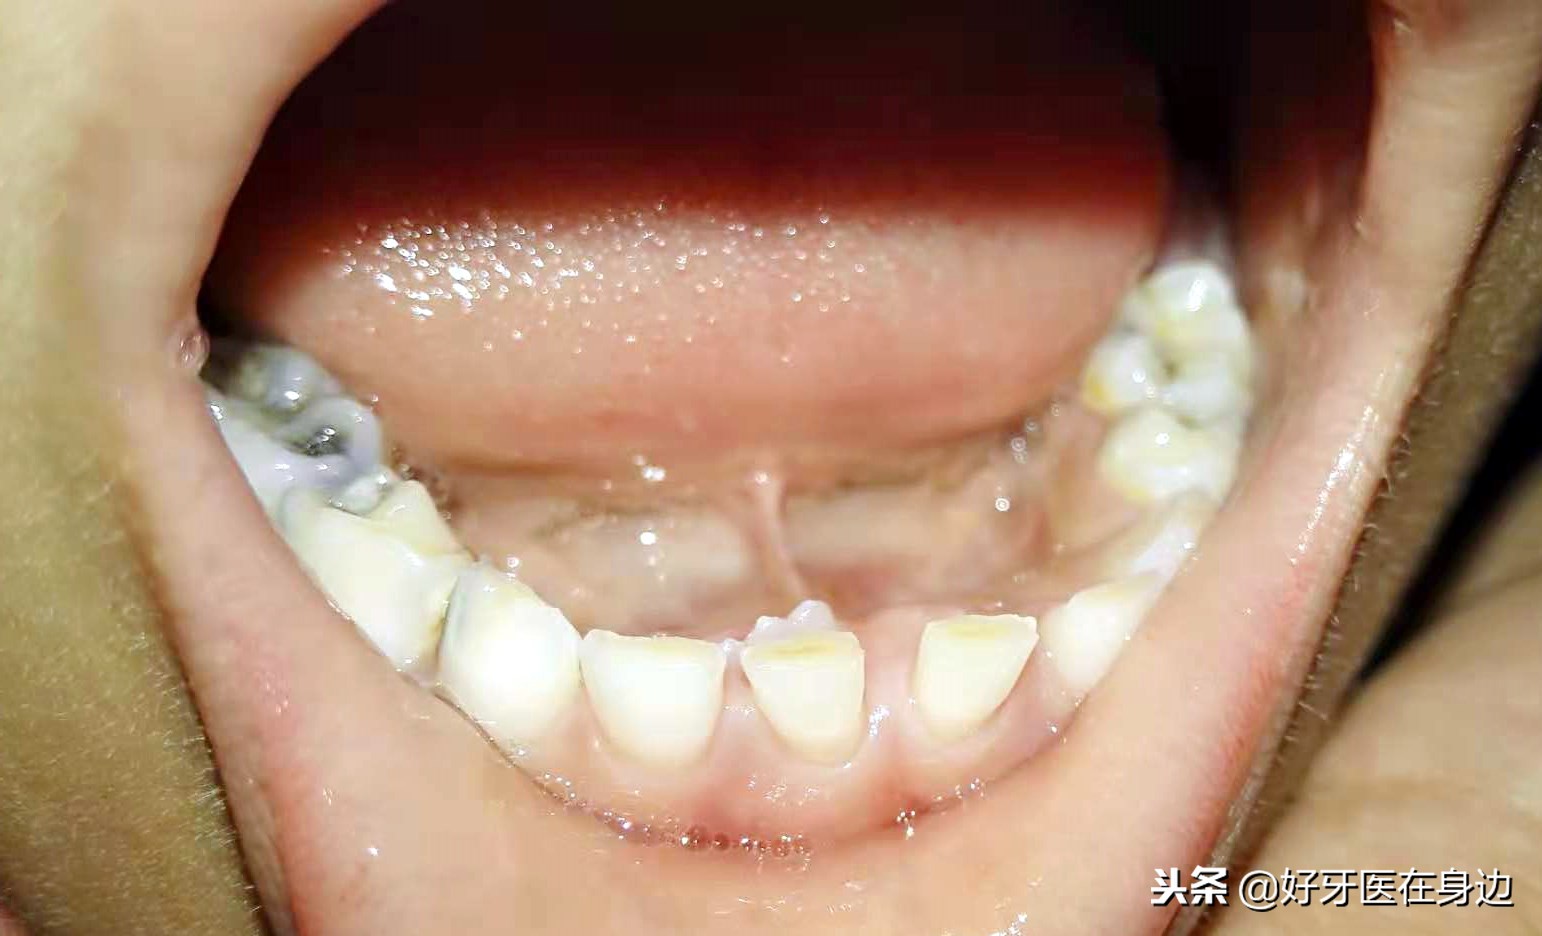

双排牙

那么什么是“双排牙”呢?

“双排牙”是指在牙列上同时长有两排牙齿,常见于儿童换牙期间,由于乳牙未脱落,而新牙已经萌出,在牙列上呈现两排牙齿!